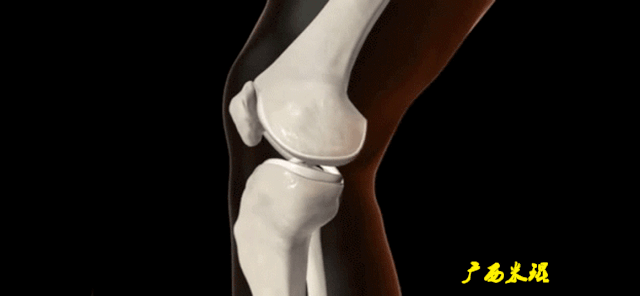

(三)ACL损伤的MRI分级

Grade1:韧带内损伤,无长度改变。

Grade2:韧带内损伤并长度延长。

Grade3:完全性韧带撕裂。

Grade1、2级是部分损伤。

Grade3级是完全损伤。